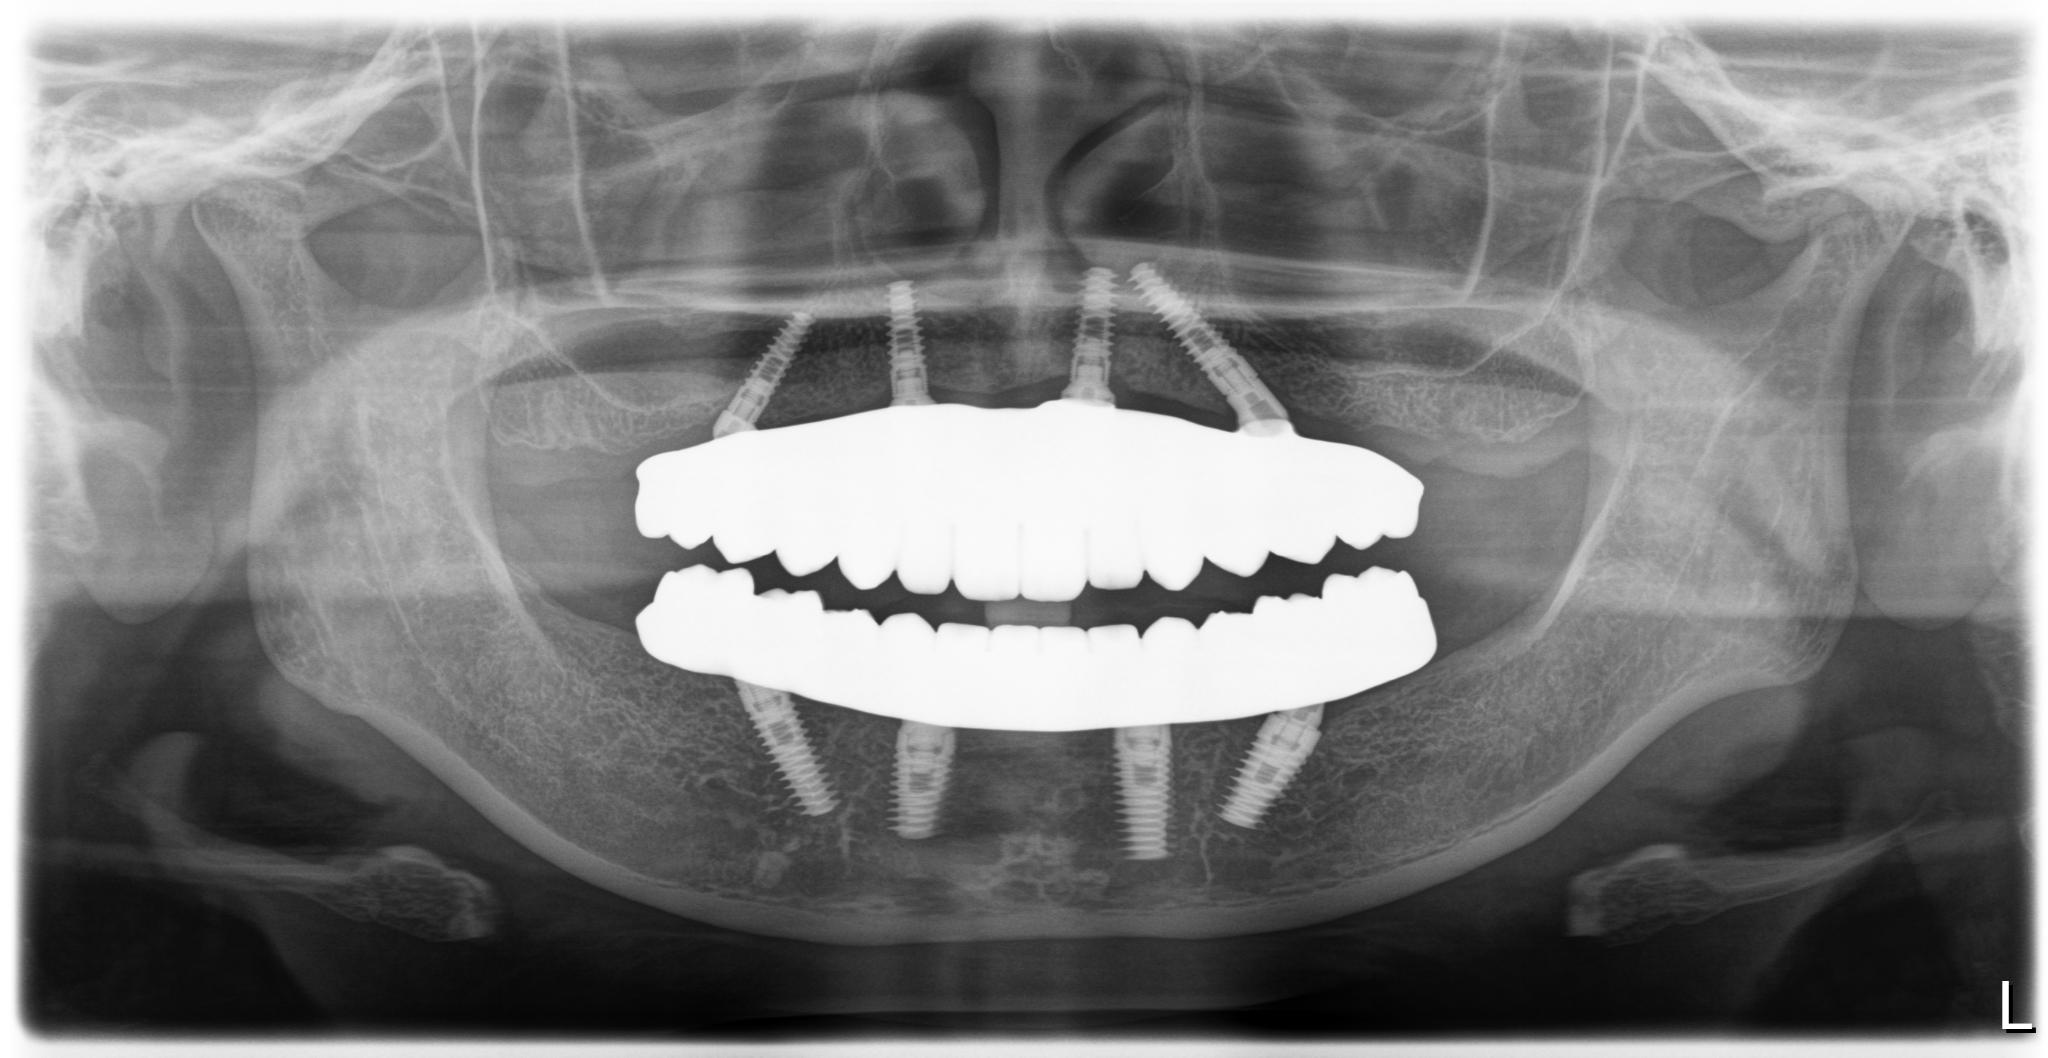

術前

内容 :上下顎オールオン4ザイゴマ0

費用 :4,989,600円

※モニター価格

期間 :半年

リスク:出血・腫れ・痺れ・痛み